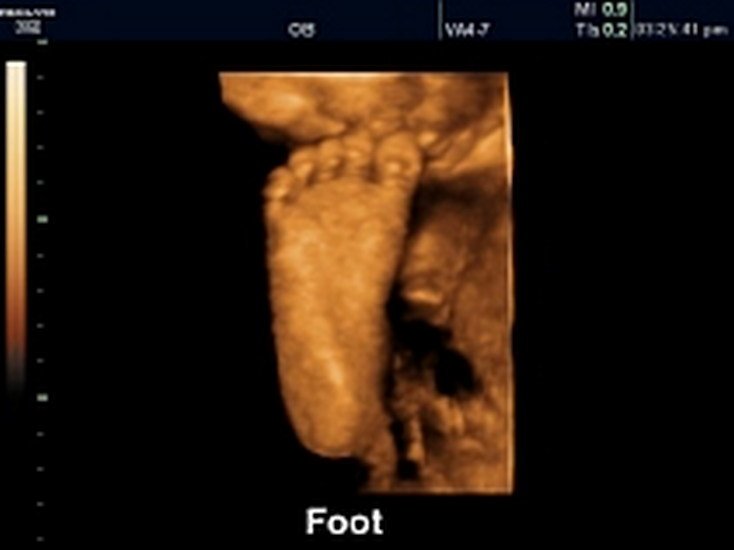

4D Sonography-Foetal Foot